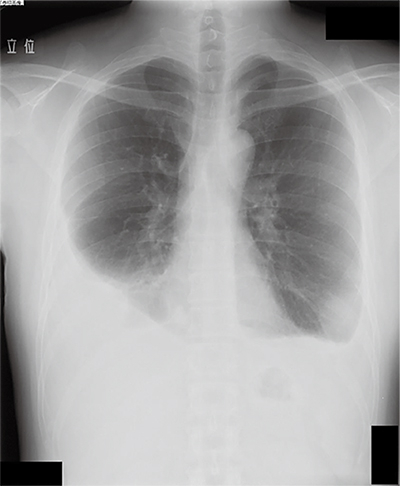

感染した寄生虫によって様々ですが、肺吸虫症では咳、血痰、胸痛などの症状を認めることが多いとされます。血液検査では好酸球増加がよく認められます。胸部エックス線写真では胸水や浸潤影など多彩な異常陰影がみられます。また、イヌ糸状虫症では無症状のことも多く、胸部エックス線写真では腫瘤陰影を認めることが多いとされます。